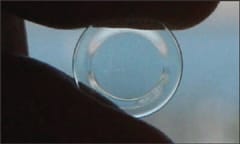

Clinicians have reported cases of patients who, after months of successful overnight corneal reshaping, present with acute episodes of ocular pain and central corneal abrasions (Figure 1). Lens inspection in these cases reveals areas of deposits on the posterior lens surface for the affected eyes.

Figure 1. Corneal abrasion caused by posterior surface lens deposits.

These reports suggest that maintaining the integrity of the posterior lens surface is important as a preventive measure. Cleaning or replacing the respective lens can help resolve signs and symptoms upon resuming lens wear.